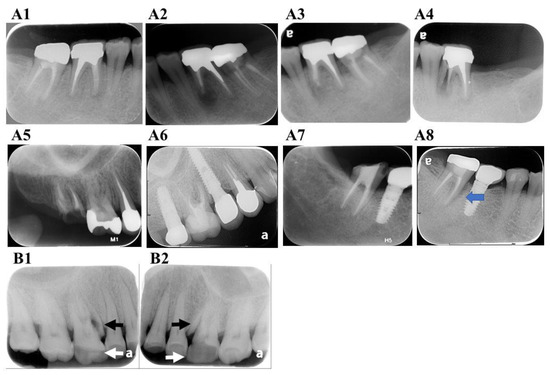

9. Radiographic Characteristics

9.1. Displacement of Fractured Fragment

9.2. Radiolucent Line within the Root Canal

9.3. Unusual Space between the Canal Wall and Intracanal Material

9.4. Widening PDL Space

9.5. Periradicular Radiolucent Halo

9.6. Angular Bony Destruction

9.7. Step-Like Bone Defect

9.8. V-Shaped Diffuse Bone Defect

9.9. Root Resorption Correspond to the Fracture Line (Figure 5F1,F2)

9.10. Widening of the Root Canal Space (Figure 5G)

9.11. Endodontic Failure after Healing has Occurred

9.12. No Evident Radiographic Finding